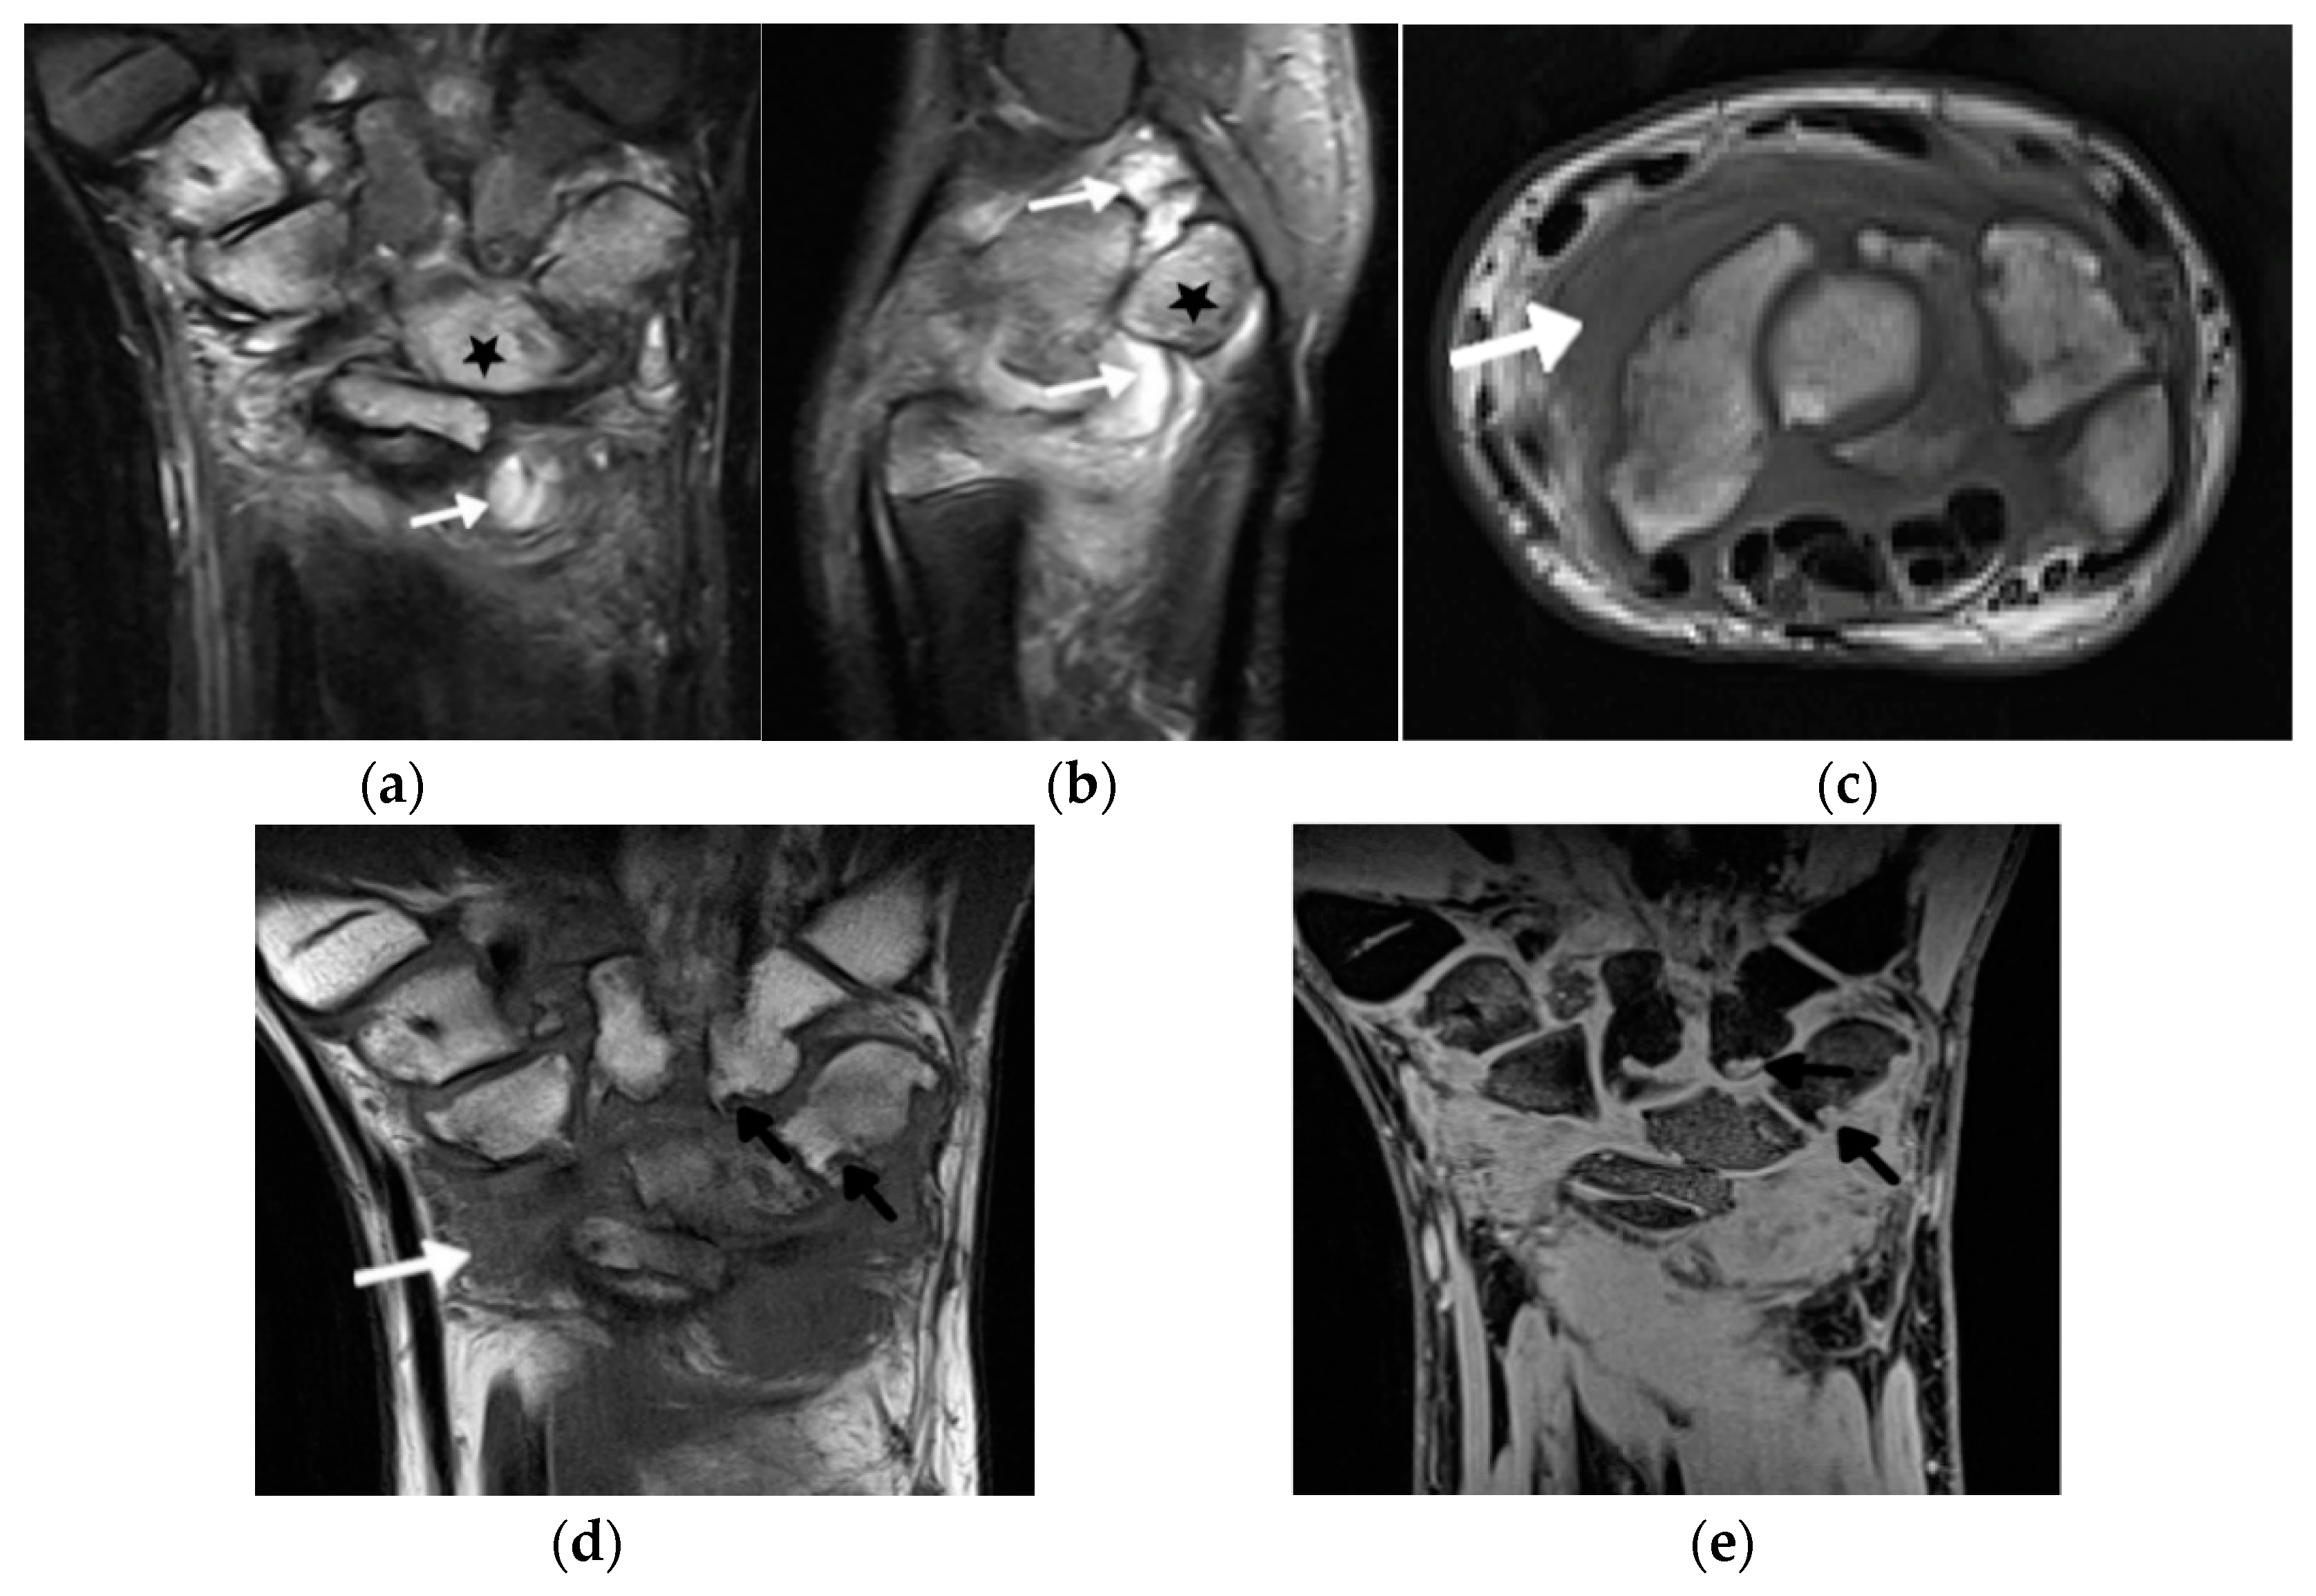

- Avenarius, D.F.M.; Nusman, C.; Malattia, C.; de Horatio, L.T.; Rosendahl, K.; Maas, M.; Müller, L.-.S.O. Current status of wrist imaging in juvenile idiopathic arthritis. Pediatr. Radiol. 2018, 48, 801–810. [Google Scholar] [CrossRef]